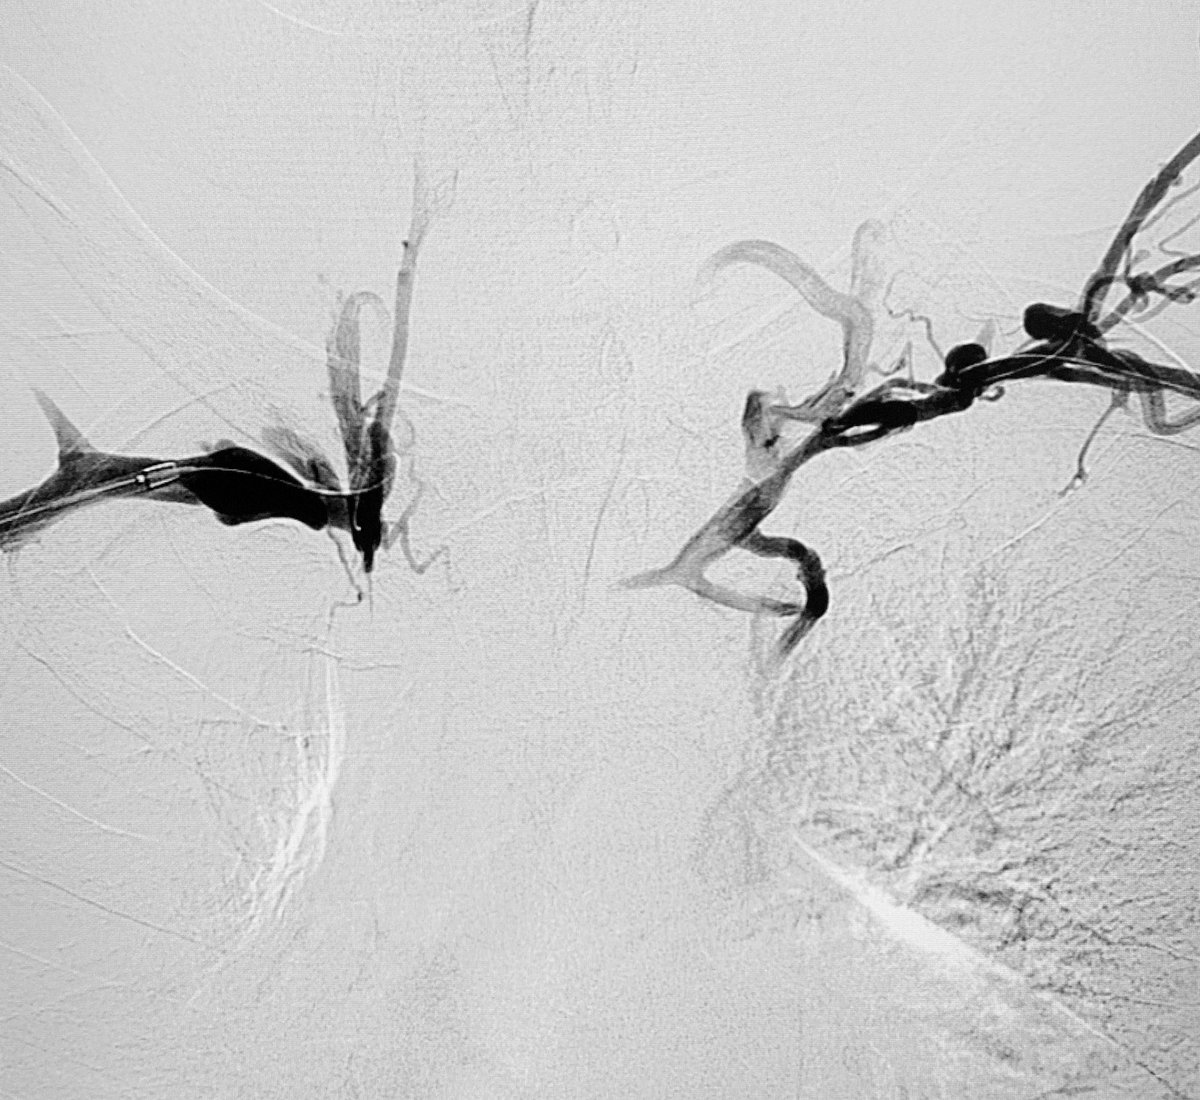

56 Y O known Chronic Liver Disease with Isolated Gastric Varices. Treated by

#Balloon#Occlusion Transvenous#Obliteration and#VascularPlug Placement#Intervention#Radiology#Makkahpic.twitter.com/0eup4cuY7x